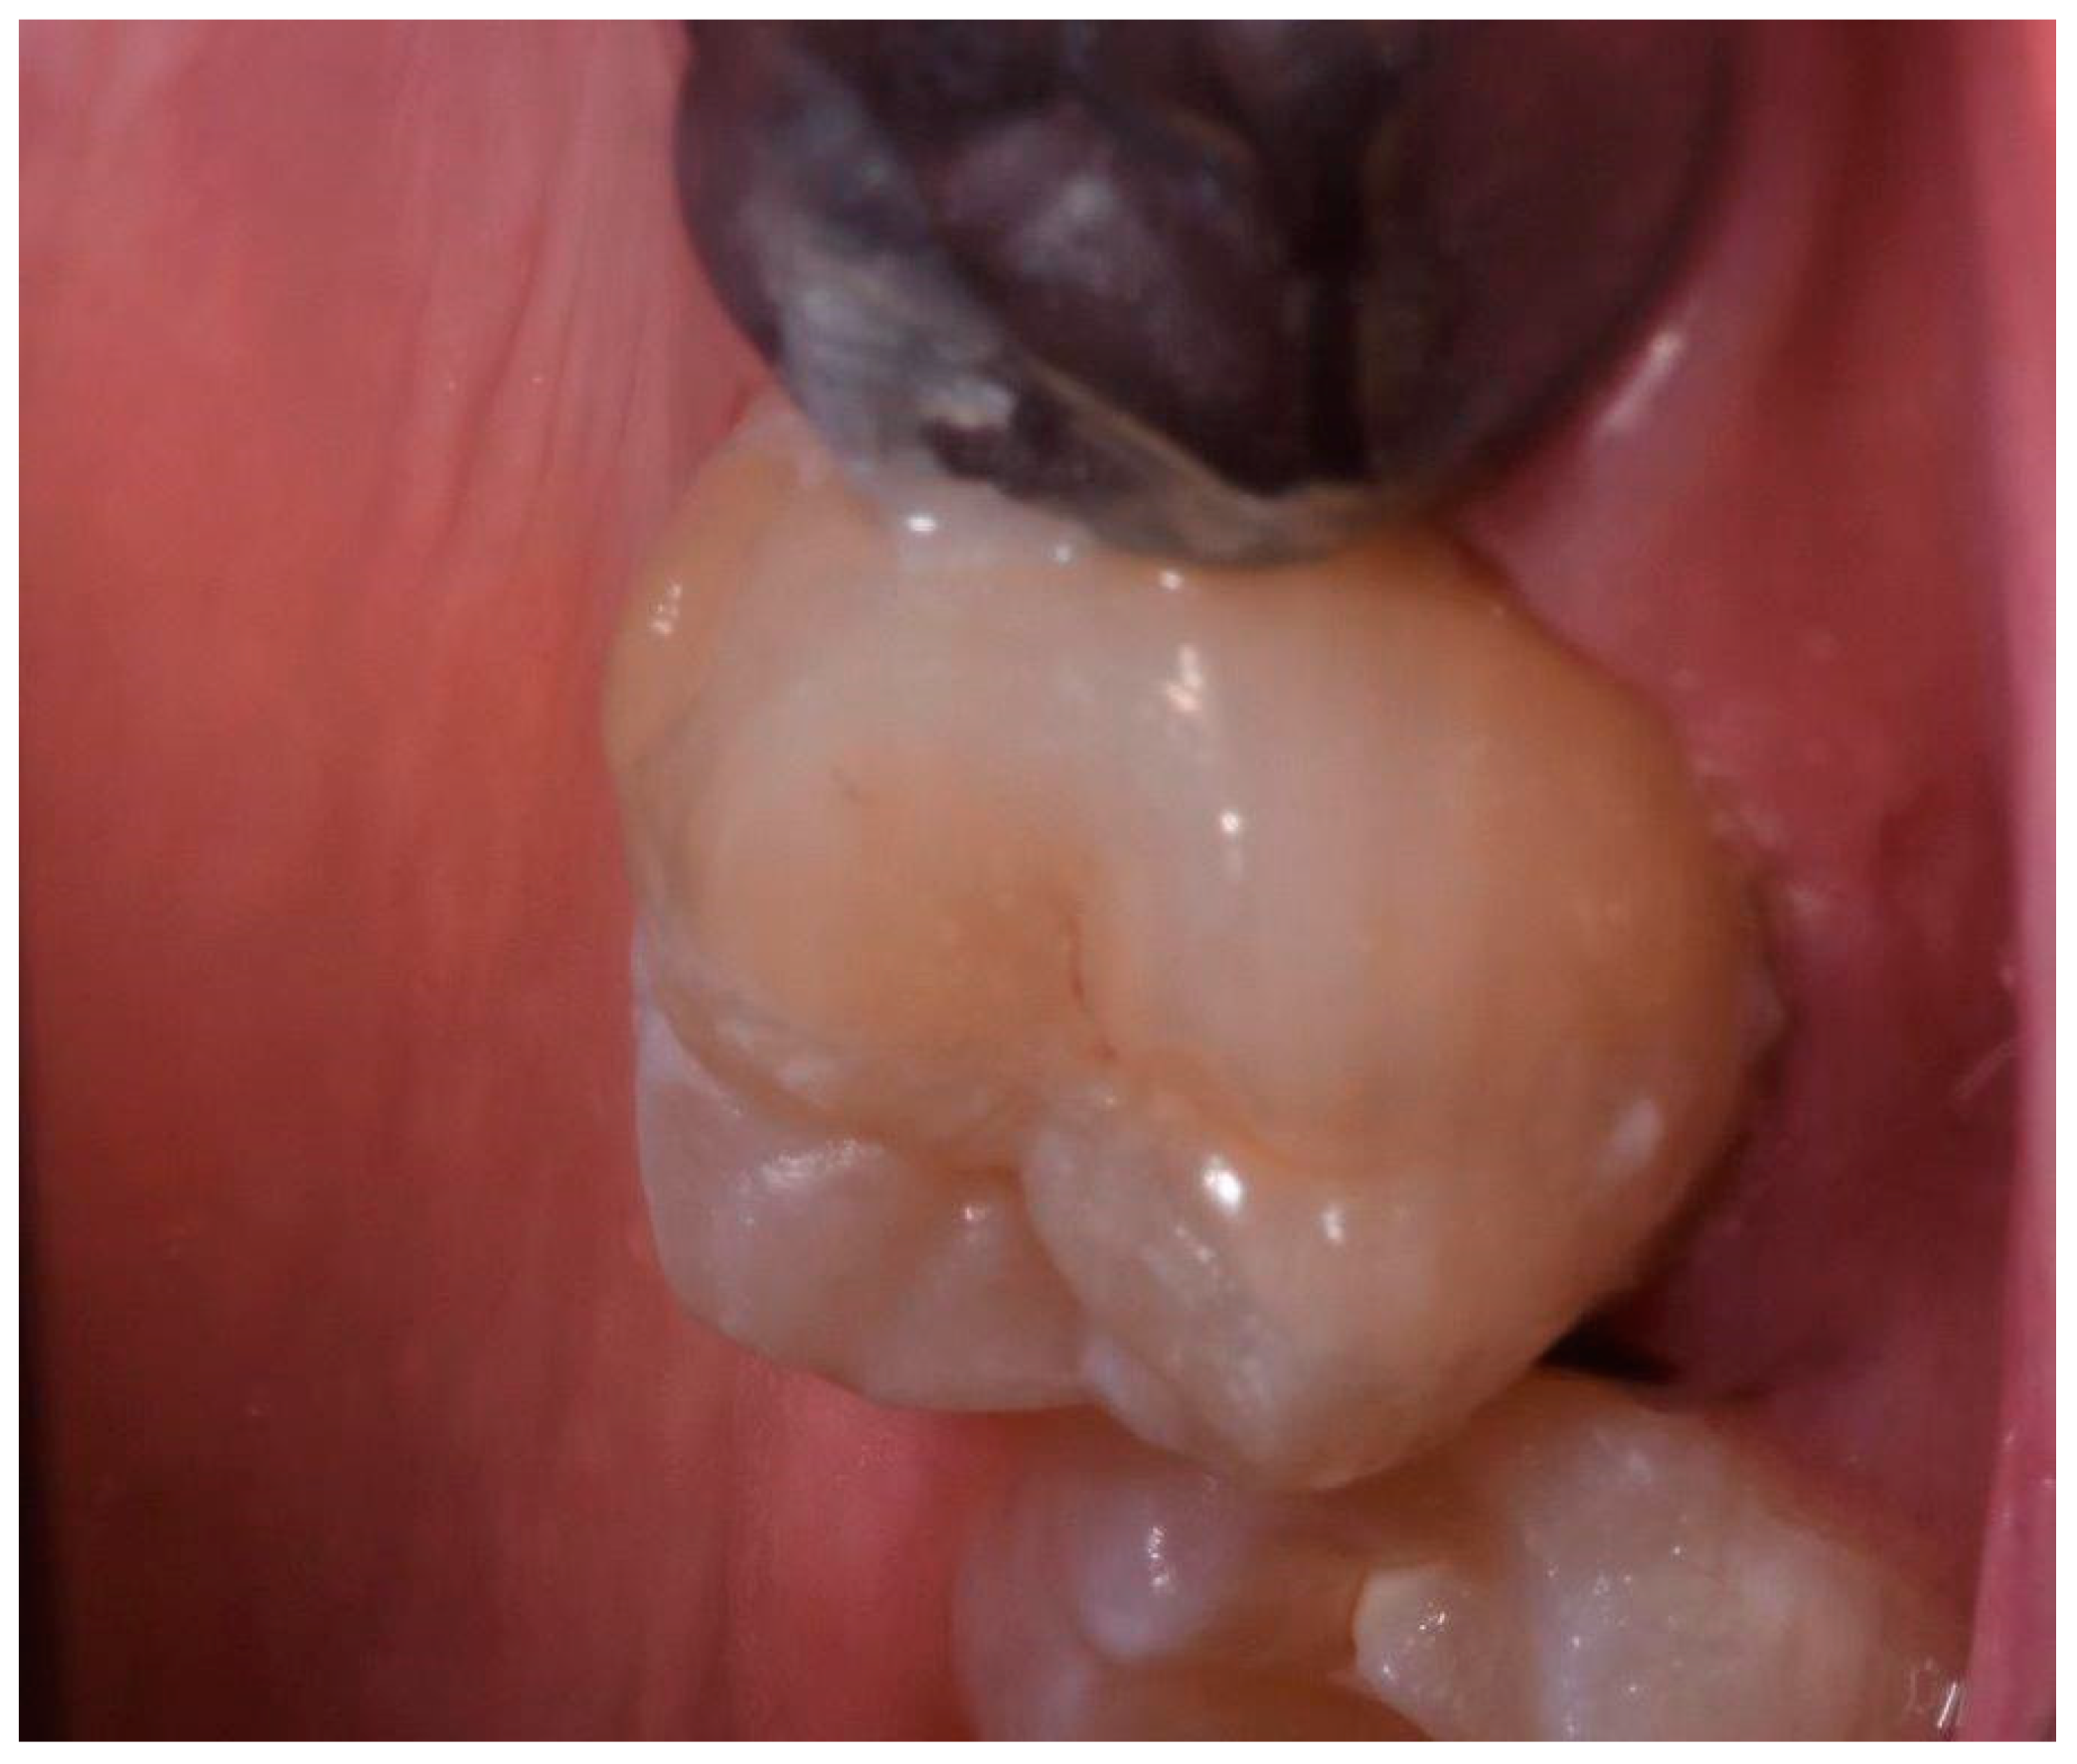

2.2. Clinical Case